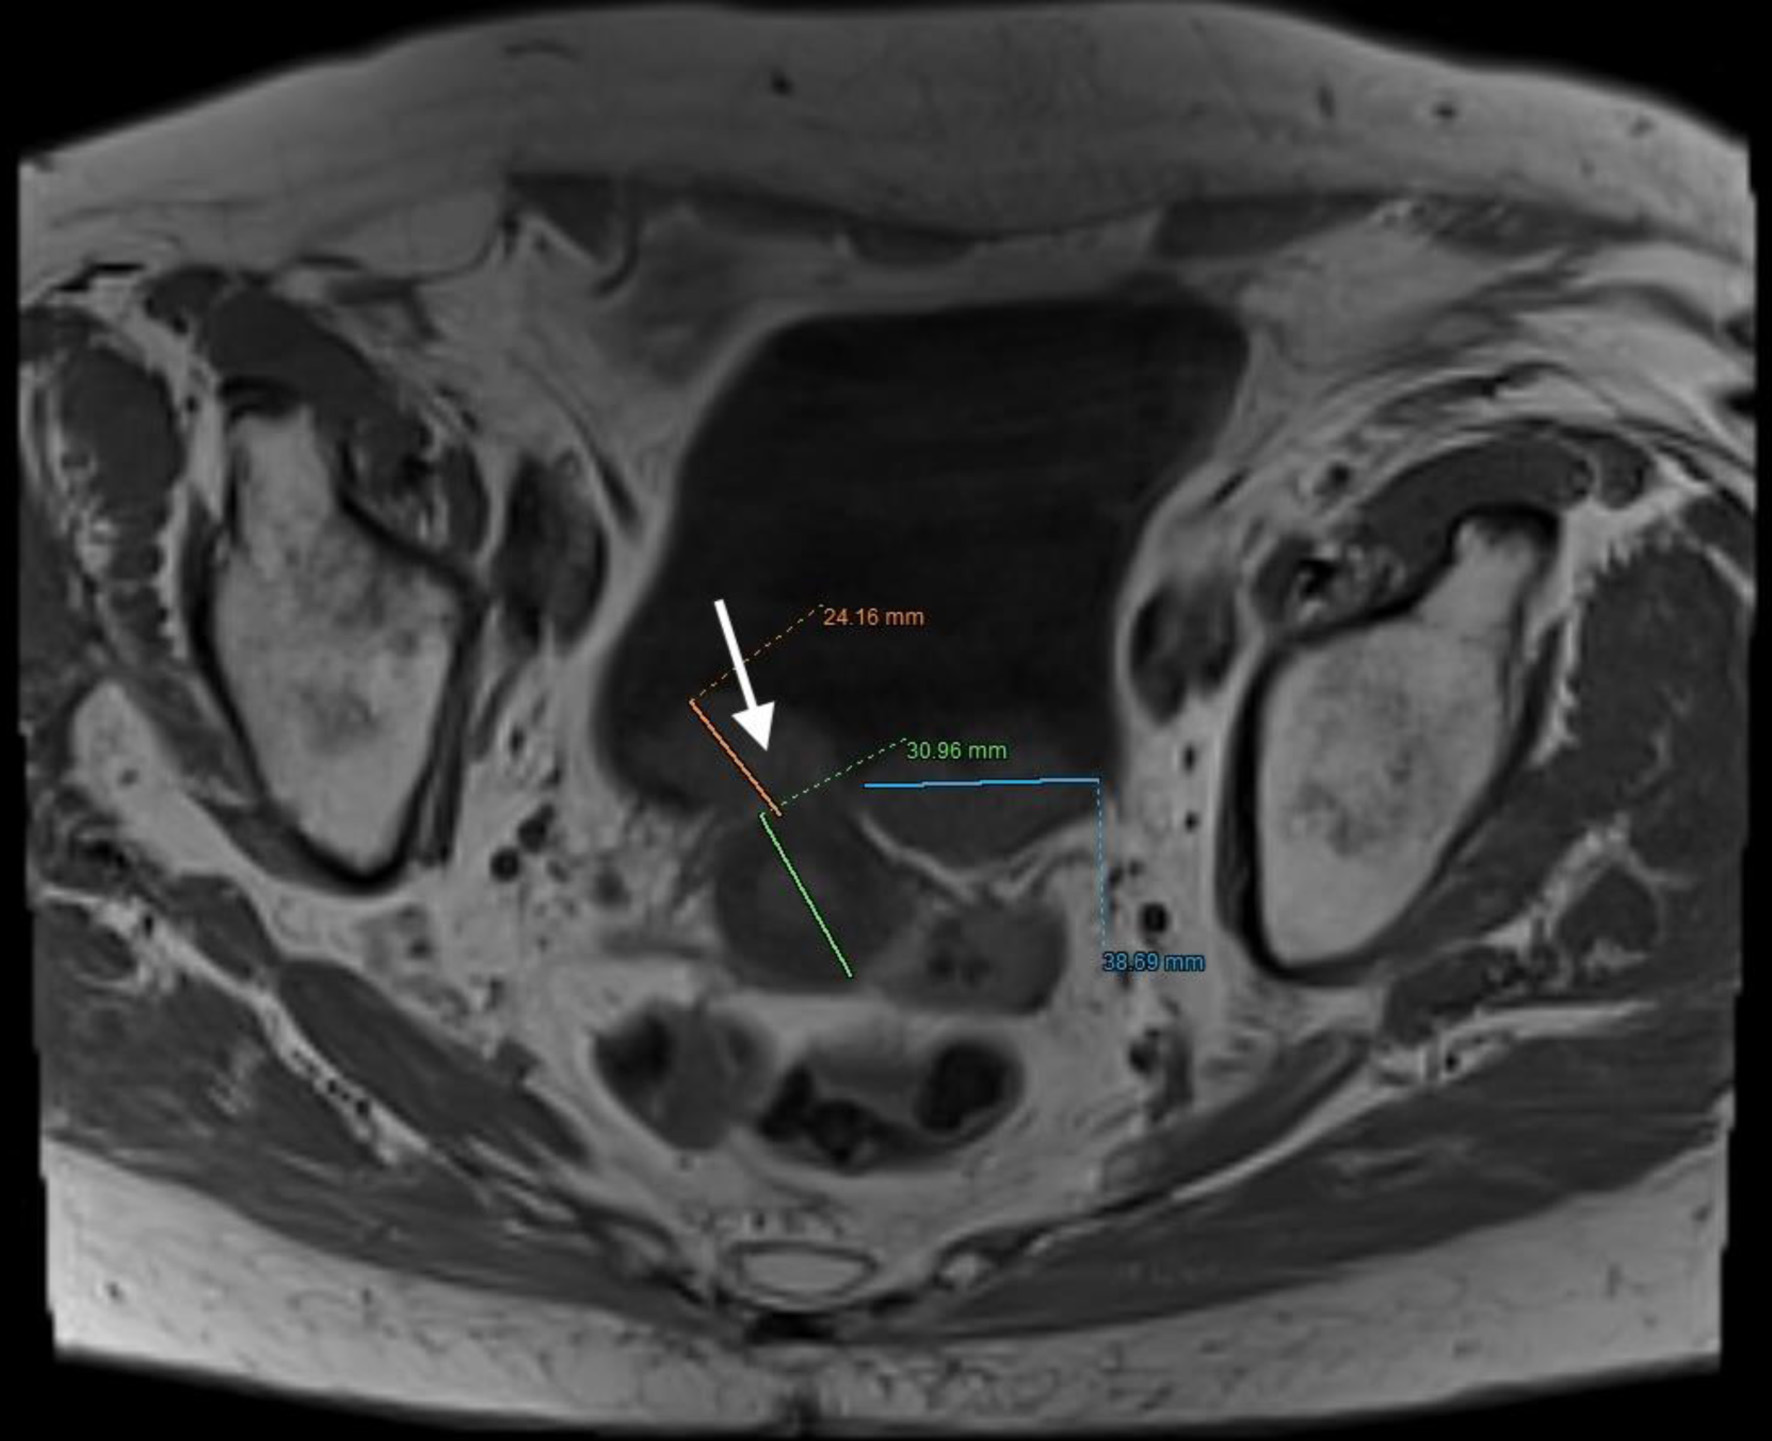

The patient, who had undergone a left nephroureterectomy 1 year earlier for urothelial carcinoma, presented again with suspected malignancy of the right upper urinary tract. Following urological consultation and instrumental evaluation (cystoscopy), urinary bladder tumors were detected, and the patient proceeded to further imaging assessment. Magnetic resonance imaging (MRI) of the upper abdomen revealed a tumor in the right kidney with invasion of the ureter and perirenal adipose tissue (Figs. 6 and 7). Lower abdominal MRI examination confirmed urinary bladder tumors with infiltration of the distal ureter and uterus (Figs. 811). Considering the patient’s clinical status, the potential aggressiveness of the malignancy, the absence of definitive histopathological confirmation of the new tumors (which could represent distinct lesions requiring separate pathological sampling), and the patient’s preference, no preoperative neoadjuvant therapy was administered. Surgery was therefore the only available therapeutic option, to which the patient provided full informed consent, despite her high-risk clinical profile and the complexity of the proposed high-risk surgical procedure. The postoperative histopathological report demonstrated high-grade renal urothelial carcinoma with contiguous extension to the ureter, urinary bladder, and bladder neck. Five of the 11 excised lymph nodes were metastatic, classifying the tumor as pT4N2Mx. Despite radiological evidence suggestive of uterine involvement, histopathological examination of the uterus and ovaries showed no malignancy; instead, polypoid endometrial hyperplasia and ovarian cysts were identified.

Figure 10. Lower abdominal magnetic resonance imaging (MRI) demonstrated an infiltrative tumor involving the urinary bladder and distal ureter (arrows 1 and 2), with extension into the uterus (arrow 3).

Figure 11. Lower abdominal magnetic resonance imaging (MRI) indicated possible infiltration of uterus (arrow).